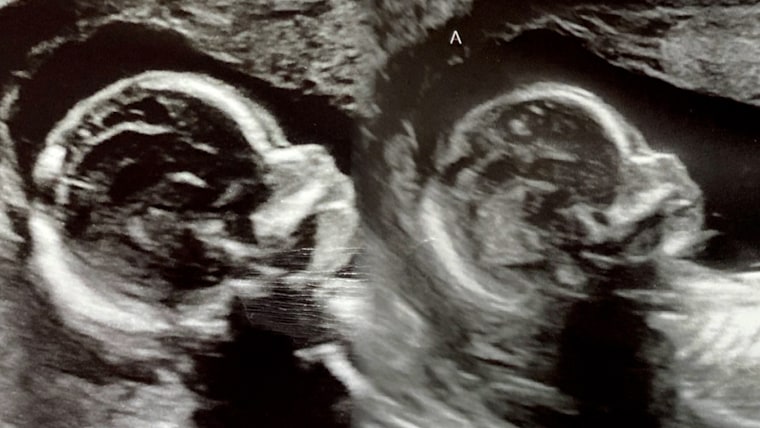

Kelsey Hatcher was born with two uteri, each with its own cervix — a condition known as uterine didelphys. She is expecting two baby girls, one in each uterus, with an official due date on Christmas Day, NBC affiliate WVTM of Birmingham reported.

Only about 3 in 1,000 women are born with two uteri, and the chances of being pregnant in both are at least 1 in a million, said Dr. Richard Davis, a specialist in obstetrics and gynecology at the University of Alabama Hospital. Davis is consulting Hatcher through her pregnancy and has assisted with most of her ultrasounds.

The babies, which are growing healthily, come from separate eggs and won’t be identical, so Davis suggested the term "fraternal twins" might be a more accurate way to describe them.